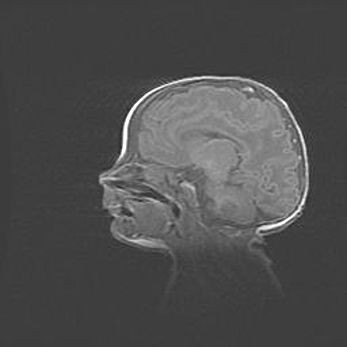

Неполная лизэнцефалия (пахигирия). Открытая гидроцефалия.

Возраст: 17 дней

Вес: 3110 г

Пол: мужской

Окружность головы: 33,5 см

Срок гестации: 35-36 недель

Лизэнцефалия—недоразвитие корковой пластинки и мозговых извилин в результате нарушения миграции нейронов коры. Поверхность мозговых полушарий гладкая. Микроскопически выявляется отсутствие нормальных слоев коры и скопление групп нейронов в подкорковом белом веществе.

Пахигирия—уменьшение числа вторичных извилин. В пораженном полушарии нервные клетки образуют толстый недифференцированный слой с неправильно расположенными нервными волокнами и группами гетеротопных клеток. Нервные клетки незрелые. Белое вещество истончено. При этом нередко аномально развит корково-спинномозговой путь.